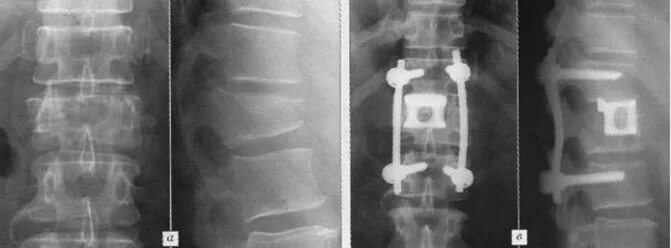

Перелом позвоночника срастается